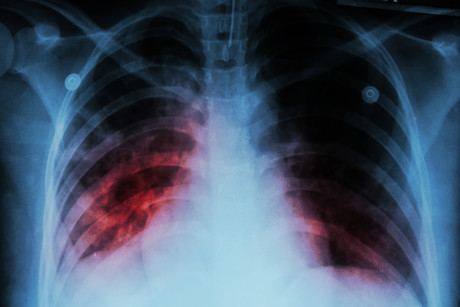

According to the World Health Organization, TB is the leading cause of death globally from a single infectious agent. Mycobacterium tuberculosis typically affects the lungs, but can also infect other sites of the body.